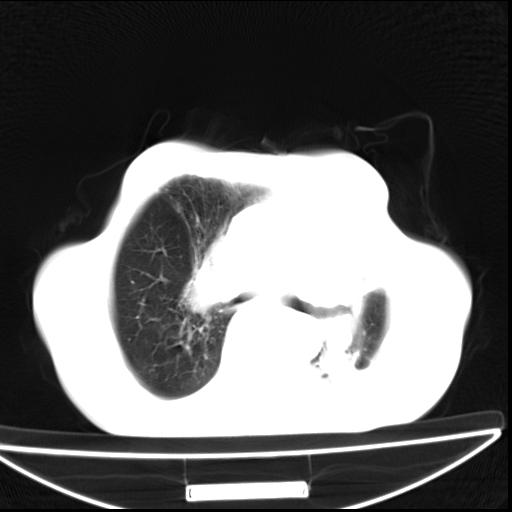

男  70岁,发烧咳嗽4天。盗汗,消瘦。无痰中带血丝,以前有肺tb病史,ct见,双肺tb,左侧胸廓塌陷,左胸膜肥厚粘连。纵隔移位,右侧胸腔积液,大家说说那个心影前左肺舌叶除了肺大炮还有炎症还是干酪性肺炎?有占位吗?我看纵隔淋巴结也大。

1)两肺继发性肺结核并左肺上叶肺不张,支气管扩张。2)双侧胸膜炎(胸膜增厚+少量胸腔积液)。

两肺继发性肺结核并感染,左肺上叶肺不张。建议ct增强。